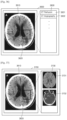

- the display unit 520 displays a first image including an object.

- the first image is a medical image of the object and may be any medical image captured to diagnose a disease, such as a tomography image like an MRI image or a CT image, an X-ray image, or an ultrasound image.

- the first image is an MRI image of a head of a patient.

- the UI unit 530 When a first region in the first image is selected, the UI unit 530 outputs a first list including at least one protocol applied while scanning the object, and receives a selection on a first protocol included in the first list.

- the first list output by the UI unit 530 is displayed through the display unit 520.

- the first list may include at least one CT protocol.

- the first list may include at least one MRI protocol.

- the first list may include at least one MRI protocol and at least one CT protocol.

- the first list may include a list of images corresponding to a protocol applied while scanning the object.

- the UI unit 530 generates a UI screen including the first list and outputs the UI screen to the display unit 520. Then, the display unit 520 may display the UI screen. A user may see the first list displayed through the display unit 520 and select a predetermined protocol through the UI unit 530.

- the control unit 510 may control a second image reconstructed by using image data obtained by applying the first protocol to be overlaid and displayed on the first region of the first image.

- a plurality of partial regions may be selected from the first image.

- a predetermined protocol may be individually selected for the partial regions.

- the control unit 510 may overlay and display reconstructed images corresponding to the individual protocols selected for the partial regions, on the first region of the first image.